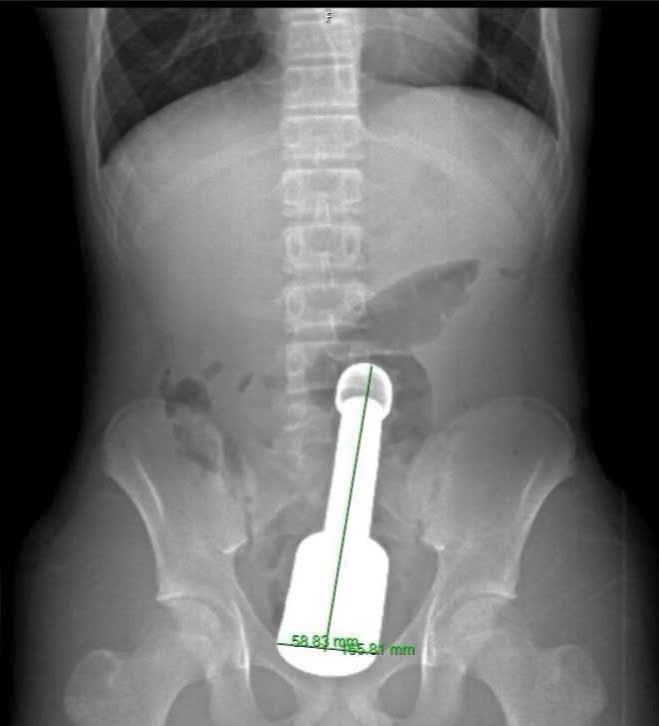

Bệnh nhân N.K.N (15 tuổi, Hà Đông, Hà Nội) nhập viện trong đêm với biểu hiện đau tức dữ dội vùng hạ vị. Kết quả chẩn đoán hình ảnh xác định một dị vật kim loại kích thước lớn mắc kẹt sâu trong trực tràng, gây chèn ép các cơ quan vùng chậu. Đây là tình huống tiềm ẩn nhiều nguy cơ biến chứng nặng nề nếu xử trí không thận trọng.

Hình ảnh phim chụp X. quang cho bệnh nhân

Trên cơ sở hội chẩn thống nhất, kíp phẫu thuật Khoa Ngoại tiêu hóa đã triển khai phương án lấy dị vật qua đường hậu môn, tránh phải mổ mở ổ bụng. Các bác sĩ phải xử lý thận trọng từng thao tác kỹ thuật nhằm giảm áp lực hút phía trên dị vật và bảo vệ cơ thắt hậu môn. Thử thách đặt ra là cực lớn: Chiếc chày không chỉ to (đường kính 6cm là giới hạn cực đại đối với cơ thắt hậu môn của một thiếu niên) mà còn rất nặng và tạo ra "hiệu ứng chân không" phía trên đỉnh dị vật, khiến nó bị hút chặt vào lòng ruột.

Sau hơn 45 phút, chiếc chày dài 18cm với đường kính 6cm đã được rút ra hoàn toàn qua đường hậu môn mà không cần phải mổ phanh ổ bụng — một thành công ngoài mong đợi về mặt bảo tồn chức năng cho bệnh nhi.